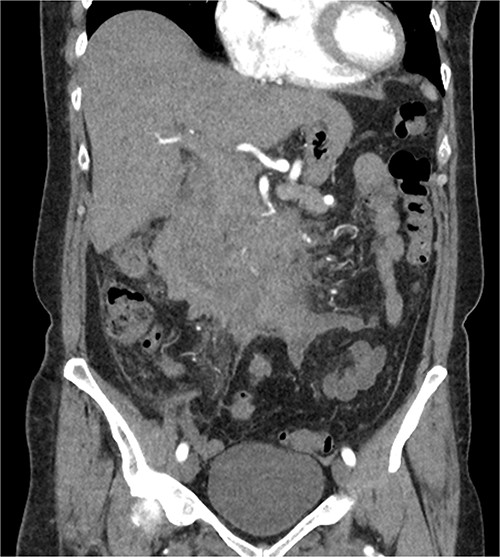

The radiologist suggested a computer tomography (CT) scan to further explore the potential causes for this fluid. The CT abdomen and pelvis revealed extensive oedema and induration surrounding the duodenum with a complex hyperdense fluid, extending from this site to the paracolic gutters and into the pelvis. While these findings are suspicious of a paraduodenal hemorrhage from a ruptured duodenal ulcer and hemoperitoneum, they were not typical for perforated duodenal ulcer or erosion into the blood vessels. Differentials were an infiltrating mass either fibrotic or of a lymphoproliferative origin. However, this could not explain the complex fluid in the abdomen (Figs 1 and 2).

CT abdomen, axial view. Hyperdense fluid centered around the duodenum and tracking into the paracolic gutters. Appearance concerning for paraduodenal hemorrhage, infiltrating mass was considered less likely.